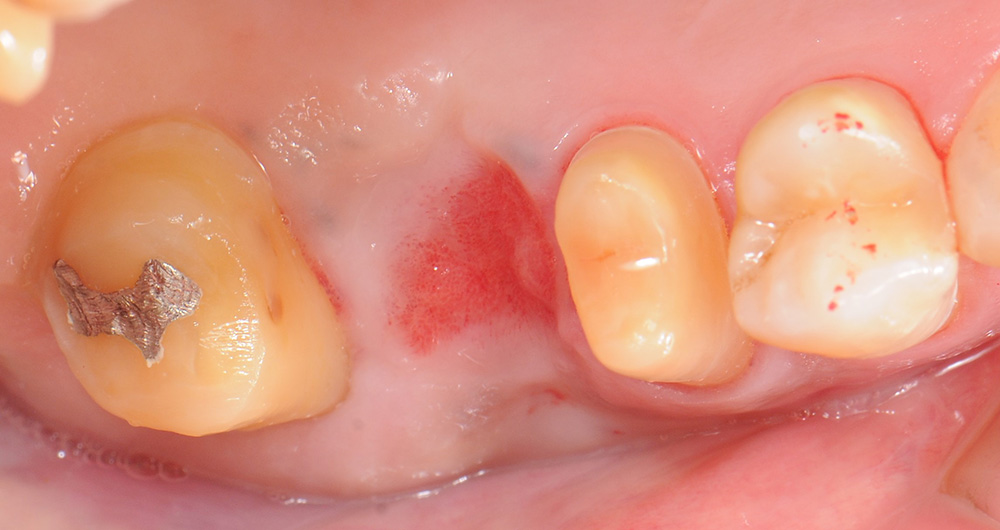

case5 症例(抜歯・歯周形成外科+セラミックブリッジ)

治療前

治療中

治療後

| 費用(税込み) | セラミック:154,000円×2本、ポンティック:77,000円 |

|---|---|

| メリット・デメリット | デメリット 歯質を削合する必要がある |

| 治療回数 | 7-8回(根管治療は別) |

| 主訴 | 歯肉が腫れた |